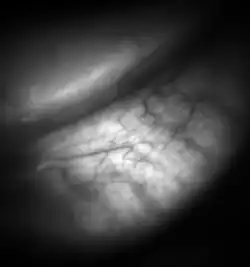

![Meibomian glands in the lower eyelid imaged under amber light to show vasculature support and the gland structure [epiCam].](./Meibomian-glands.png)